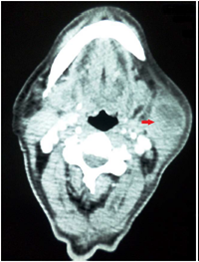

En el inicio del segundo mes de tratamiento, apareció una tumoración submandibular similar a una adenomegalia (figura 6). Se practicóbiopsia por escisión y de piel, cuya evaluación histopatológica reportócompromiso dérmico por infiltrado linfohistiocitario con tendencia a la formación de granulomas, en tanto que la tinción de ZN mostró formas bacilares fragmentadas. La tumoración no requirió manejo adicional y se interpretó como una reacción paradójica.